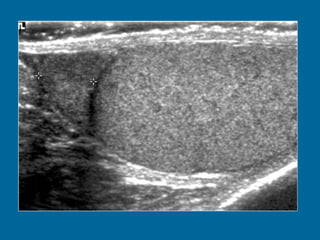

Transverse US scan of the testis shows a normal transmediastinal artery (arrow) as a linear hypoechoic band. Color Doppler flow US (not shown) revealed flow through the vessel.

Transverse US scanof the testis shows a normal transmediastinal artery (arrow) as a linear hypoechoic band. Color Doppler flow US (not shown) revealed flow through the vessel.